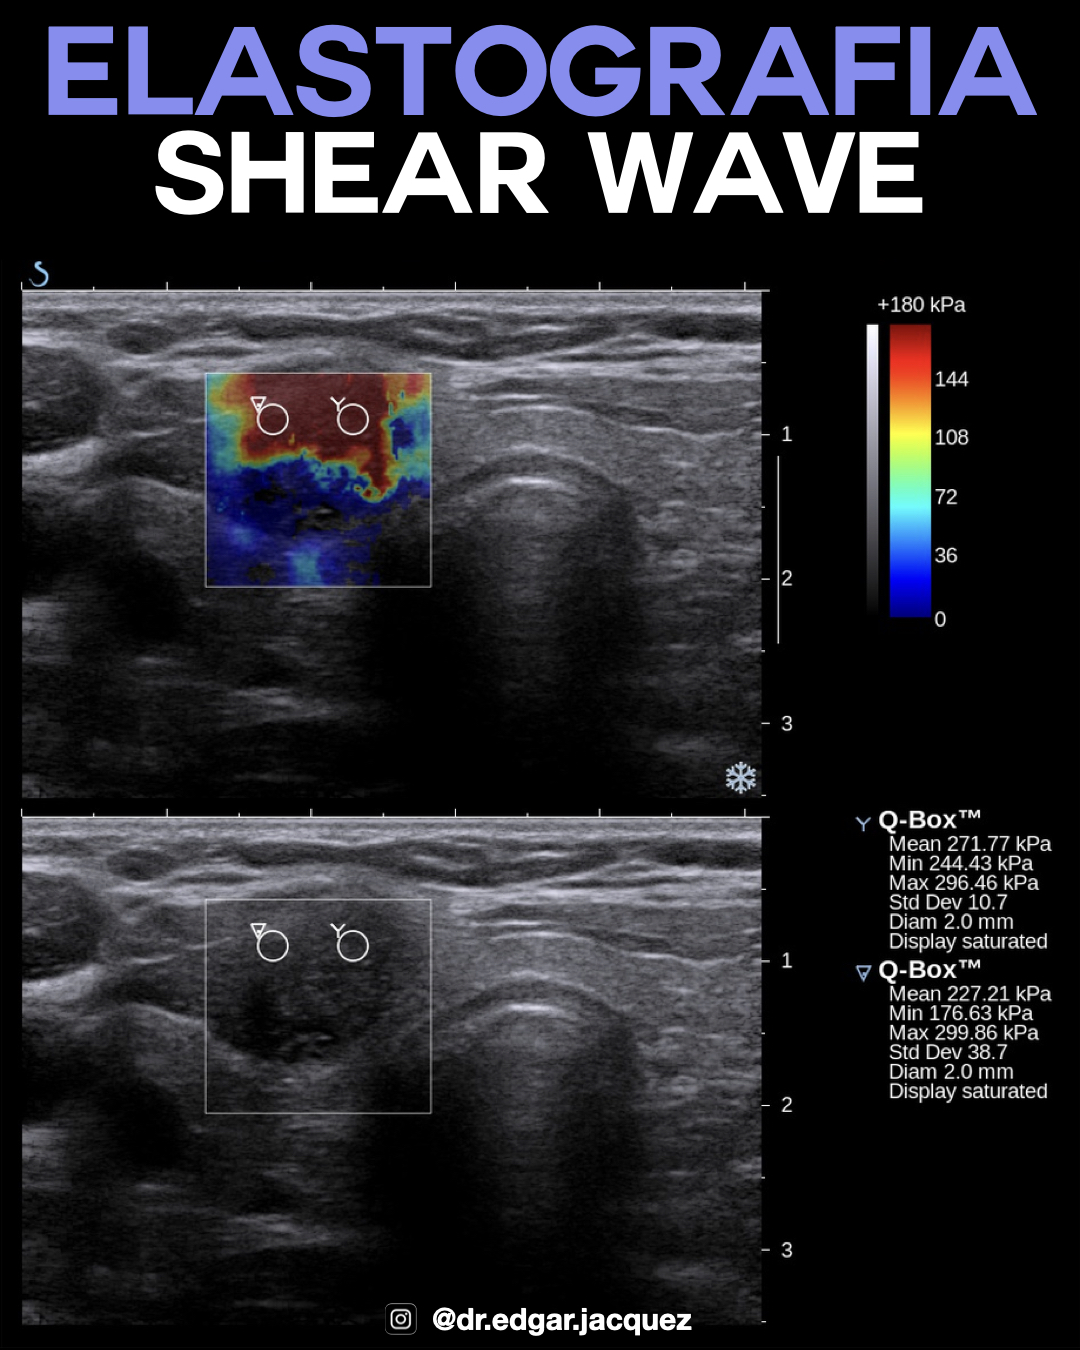

Shear Wave Elastography (SWE)

Técnica cuantitativa que mide la velocidad de propagación de las ondas de corte en m/s o la elasticidad en kPa. Velocidades > 2.6 m/s o elasticidades > 65 kPa se asocian fuertemente con procesos infiltrativos malignos.

Nota: Es particularmente útil para elevar o disminuir la sospecha en nódulos con citología indeterminada (Bethesda III/IV) y para predecir malignidad en población pediátrica sin recurrir a PAAF inmediata.